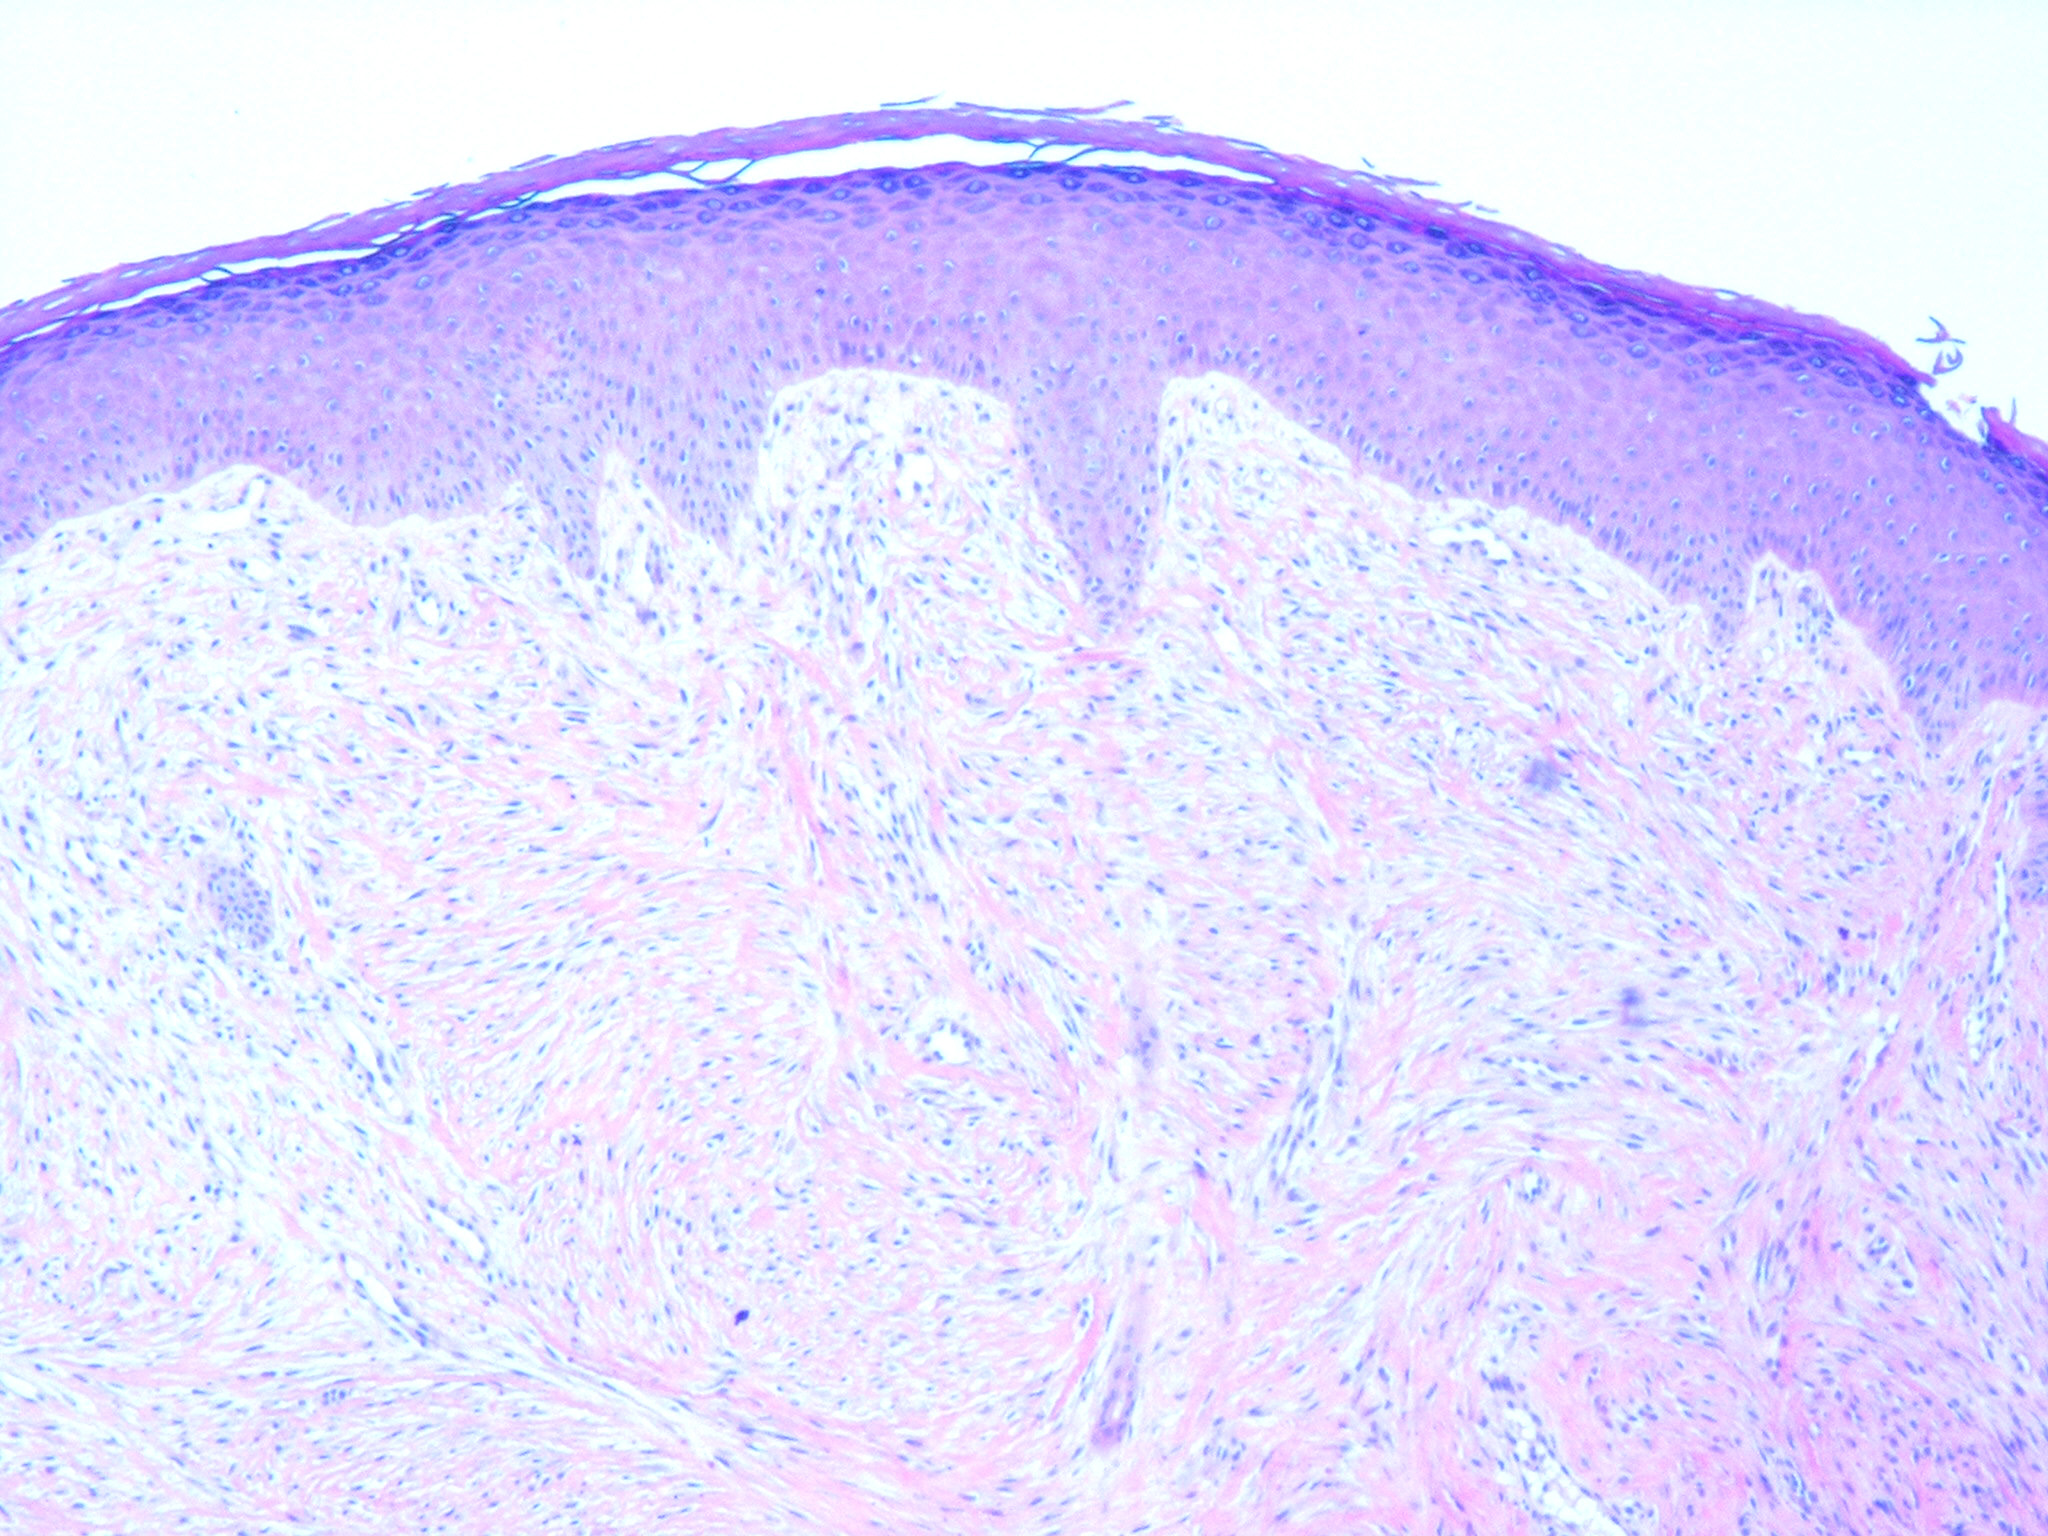

Infantile digital fibroma = الليفوم على الاصبع الطفلي